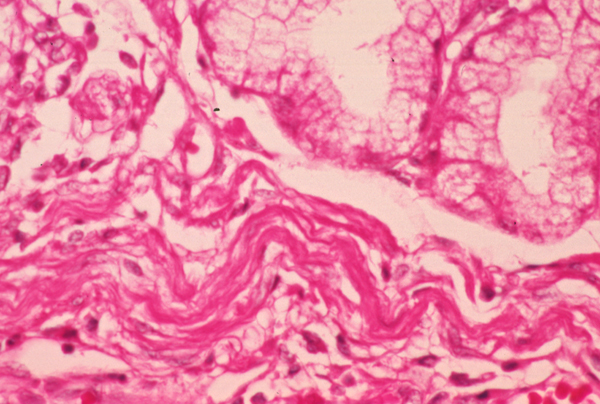

049